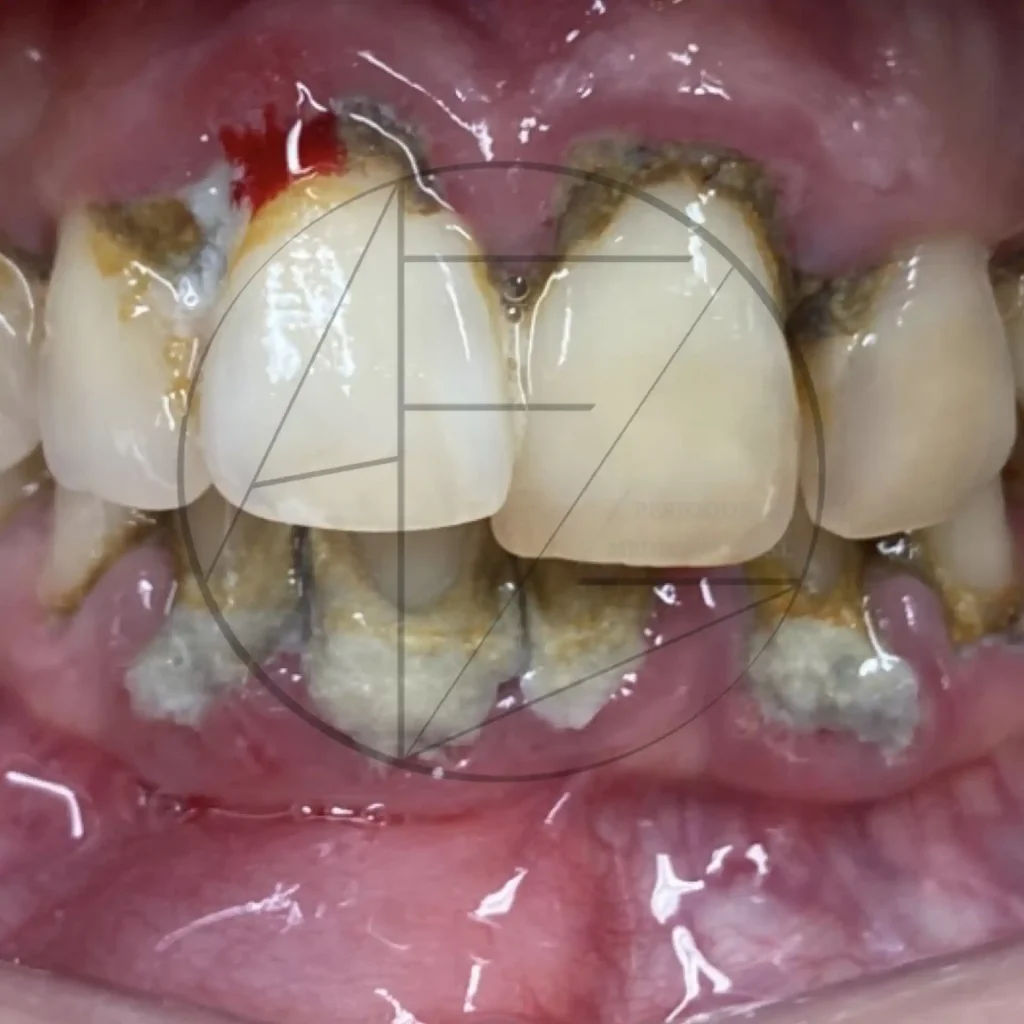

Casos clínicos

Fotos clínicas

Periodonitis